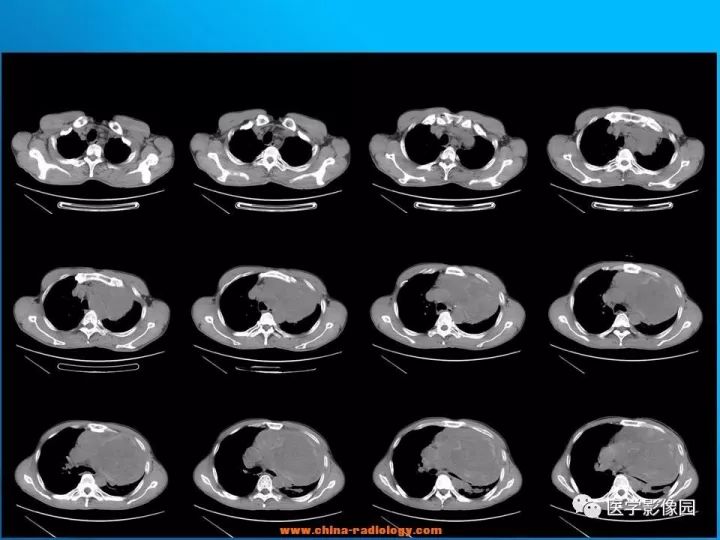

【病例】纵隔恶性神经鞘瘤1例CT

诊断结果:恶性神经鞘瘤

CT表现

1.肿瘤多为单发,平扫密度略低于肌肉,轮廓光整,呈类圆形或卵圆形,肿瘤较大时可为不规则形或呈分叶状,易囊变,常为囊实性,有包膜,可有钙化。

2.增强扫描多数病例肿瘤强化轻微,包膜可强化,少数病例可有较明显强化。

3.当肿块体积较大,并向周围侵犯,其内密度混杂,尤其是囊变、坏死明显;实性部分呈斑片状及网格状较明显强化;往往提示为恶性神经鞘瘤。